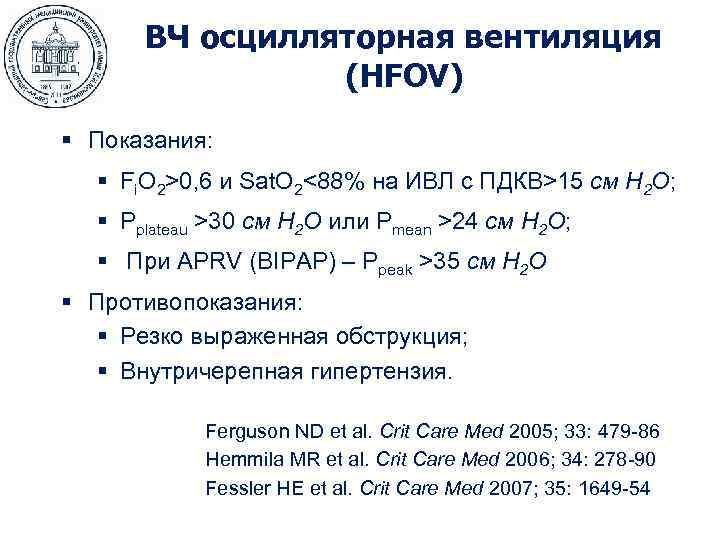

ВЧ осцилляторная вентиляция (HFOV) § Показания: § Fi. O 2>0, 6 и Sat. O 2<88% на ИВЛ с ПДКВ>15 см H 2 O; § Pplateau >30 cм H 2 O или Pmean >24 cм H 2 O; § При APRV (BIPAP) – Ppeak >35 cм H 2 O § Противопоказания: § Резко выраженная обструкция; § Внутричерепная гипертензия. Ferguson ND et al. Crit Care Med 2005; 33: 479 -86 Hemmila MR et al. Crit Care Med 2006; 34: 278 -90 Fessler HE et al. Crit Care Med 2007; 35: 1649 -54

ВЧ осцилляторная вентиляция (HFOV) § Показания: § Fi. O 2>0, 6 и Sat. O 2<88% на ИВЛ с ПДКВ>15 см H 2 O; § Pplateau >30 cм H 2 O или Pmean >24 cм H 2 O; § При APRV (BIPAP) – Ppeak >35 cм H 2 O § Противопоказания: § Резко выраженная обструкция; § Внутричерепная гипертензия. Ferguson ND et al. Crit Care Med 2005; 33: 479 -86 Hemmila MR et al. Crit Care Med 2006; 34: 278 -90 Fessler HE et al. Crit Care Med 2007; 35: 1649 -54